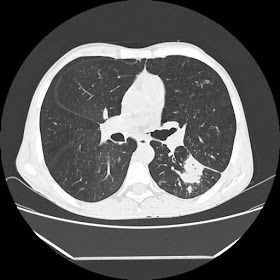

Latest HRCT images: